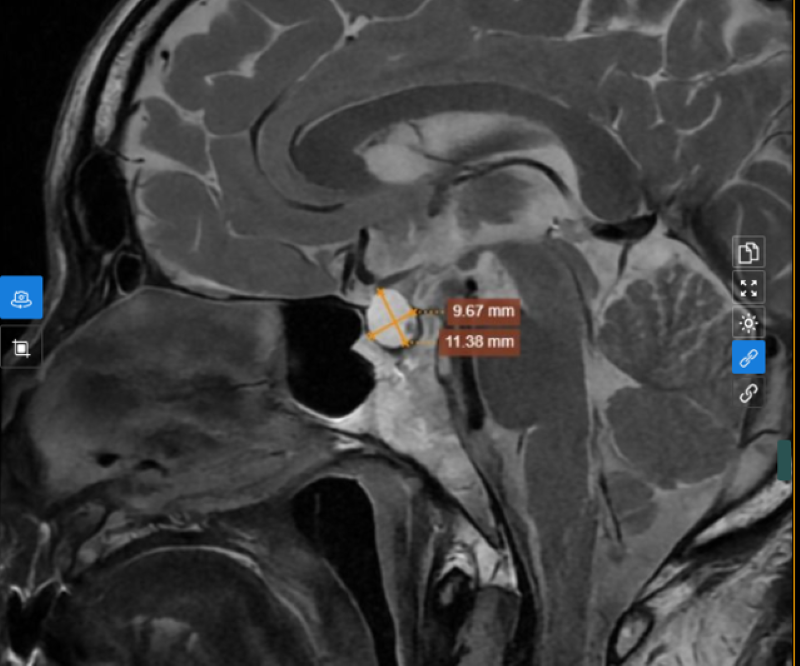

Tại đây, bác sĩ tiến hành thăm khám lâm sàng và chỉ định các kỹ thuật cận lâm sàng cần thiết phục vụ chẩn đoán. Trong đó, trên hình ảnh chụp MRI tuyến yên phát hiện có khối kích thước xấp xỉ 11x10x9mm, bờ đều ranh giới rõ, không thấy đè ép vào giao thoa thị giác, không phá hủy xương vùng hố yên, sau tiêm ngấm thuốc không đồng nhất.

Hình ảnh u vùng tuyến yên, nghĩ đến Macroadenoma (u tuyến yên lớn), bác sĩ tiếp tục chỉ định ông T. thực hiện xét nghiệm hormone nội tiết liên quan.